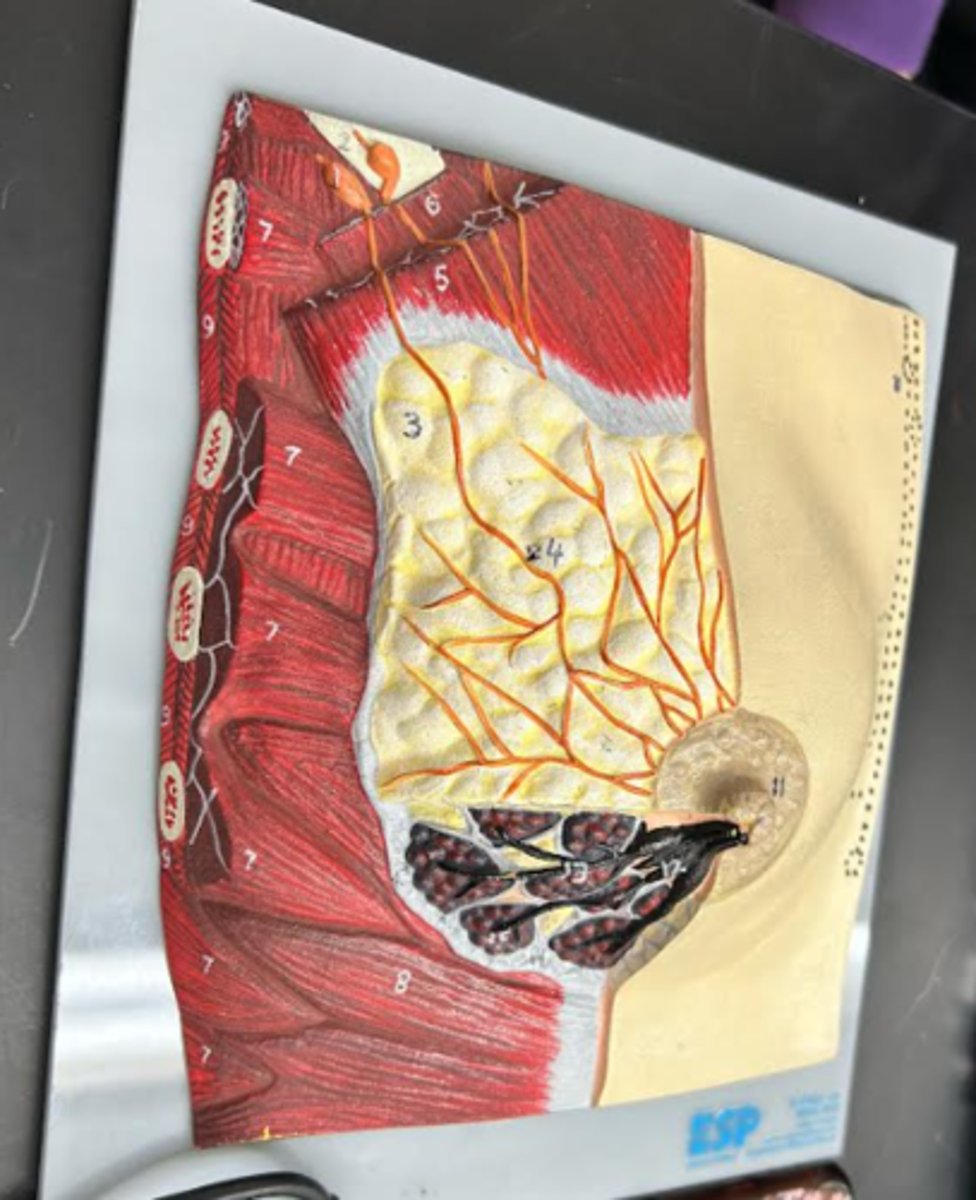

Breast

whole structure/ model

Axillary tail

Areola

Nipple

Suspensory ligament

Adipose tissue

Lactiferous sinus

Lactiferous duct

Mammary lobe

Mammary lobule